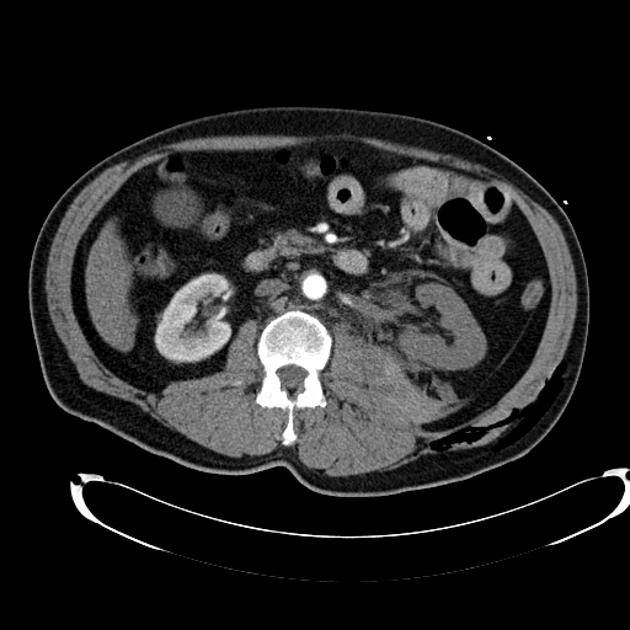

what grade?

Grade II Renal trauma

superficial laceration ≤1 cm depth not involving the collecting system (no evidence of urine extravasation)

perirenal hematoma confined within the perirenal fascia